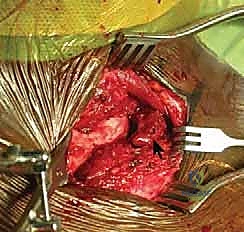

يُجري الدكتور هطيف شقاً جراحياً تجميلياً دقيقاً فوق المفصل، مع الحفاظ التام على الأعصاب الحسية والأوعية الدموية السطحية باستخدام تقنيات الجراحة الميكروسكوبية.

3. تنظيف المفصل وتقييم الغضروف

بمجرد فتح المفصل، يتم إزالة الأنسجة الندبية وبقايا الأربطة الممزقة. يتم تقييم القرص الغضروفي؛ إذا كان ممزقاً بشدة يتم استئصاله جزئياً، وإذا كان سليماً يتم الحفاظ عليه.